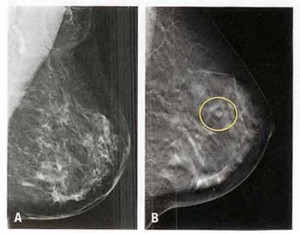

Mammografia: meglio se effettuata annualmente, non ogni tre anni

Prosegue il dibattito a colpi di studi scientifici sulla mammografia, esame essenziale per la diagnosi precoce del tumore del seno: è la volta di una ricerca condotta su oltre 50.000 donne che partecipano al programma inglese di screening del seno.